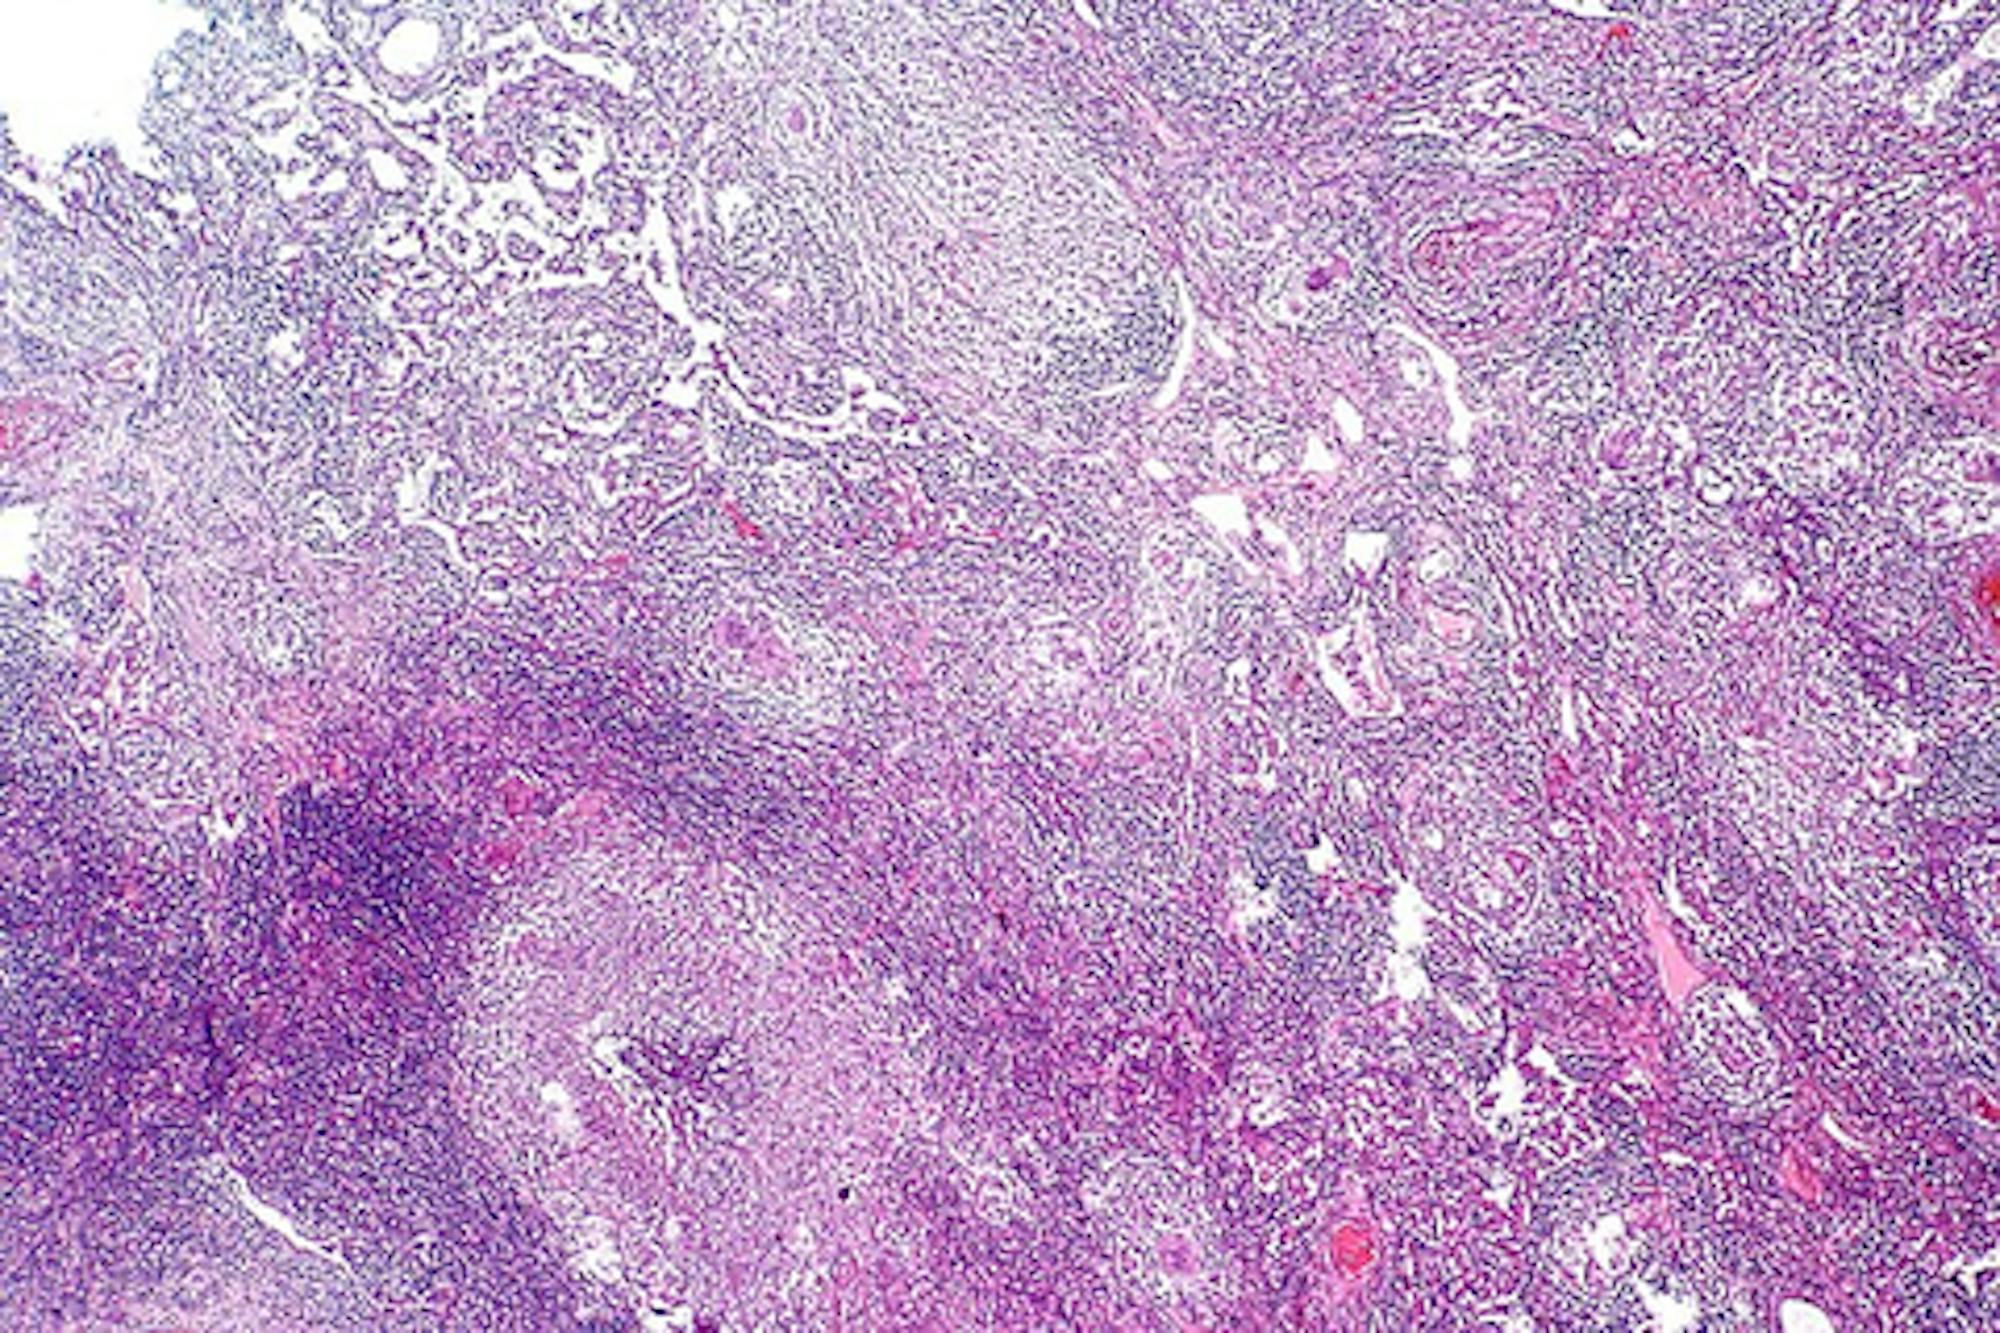

Tuberculosis is spread through respiratory droplets in the air that can come from speaking, coughing or sneezing. When an individual becomes infected with tuberculosis, the bacteria most commonly spread to the lungs, replicate and form large masses called tubercles. These tubercles can break down lung tissue and ultimately can cause permanent damage to the lungs if untreated.